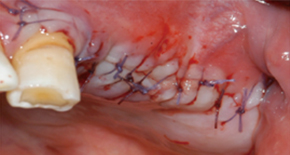

1. Exposing bone after incision

2. Forming Window in the bone

3. Elevating window & sinus membrane

4. Placing bone grafting material

5. Suture closed large surgery flappain and swelling can be minimized and quick return to daily life is possible.